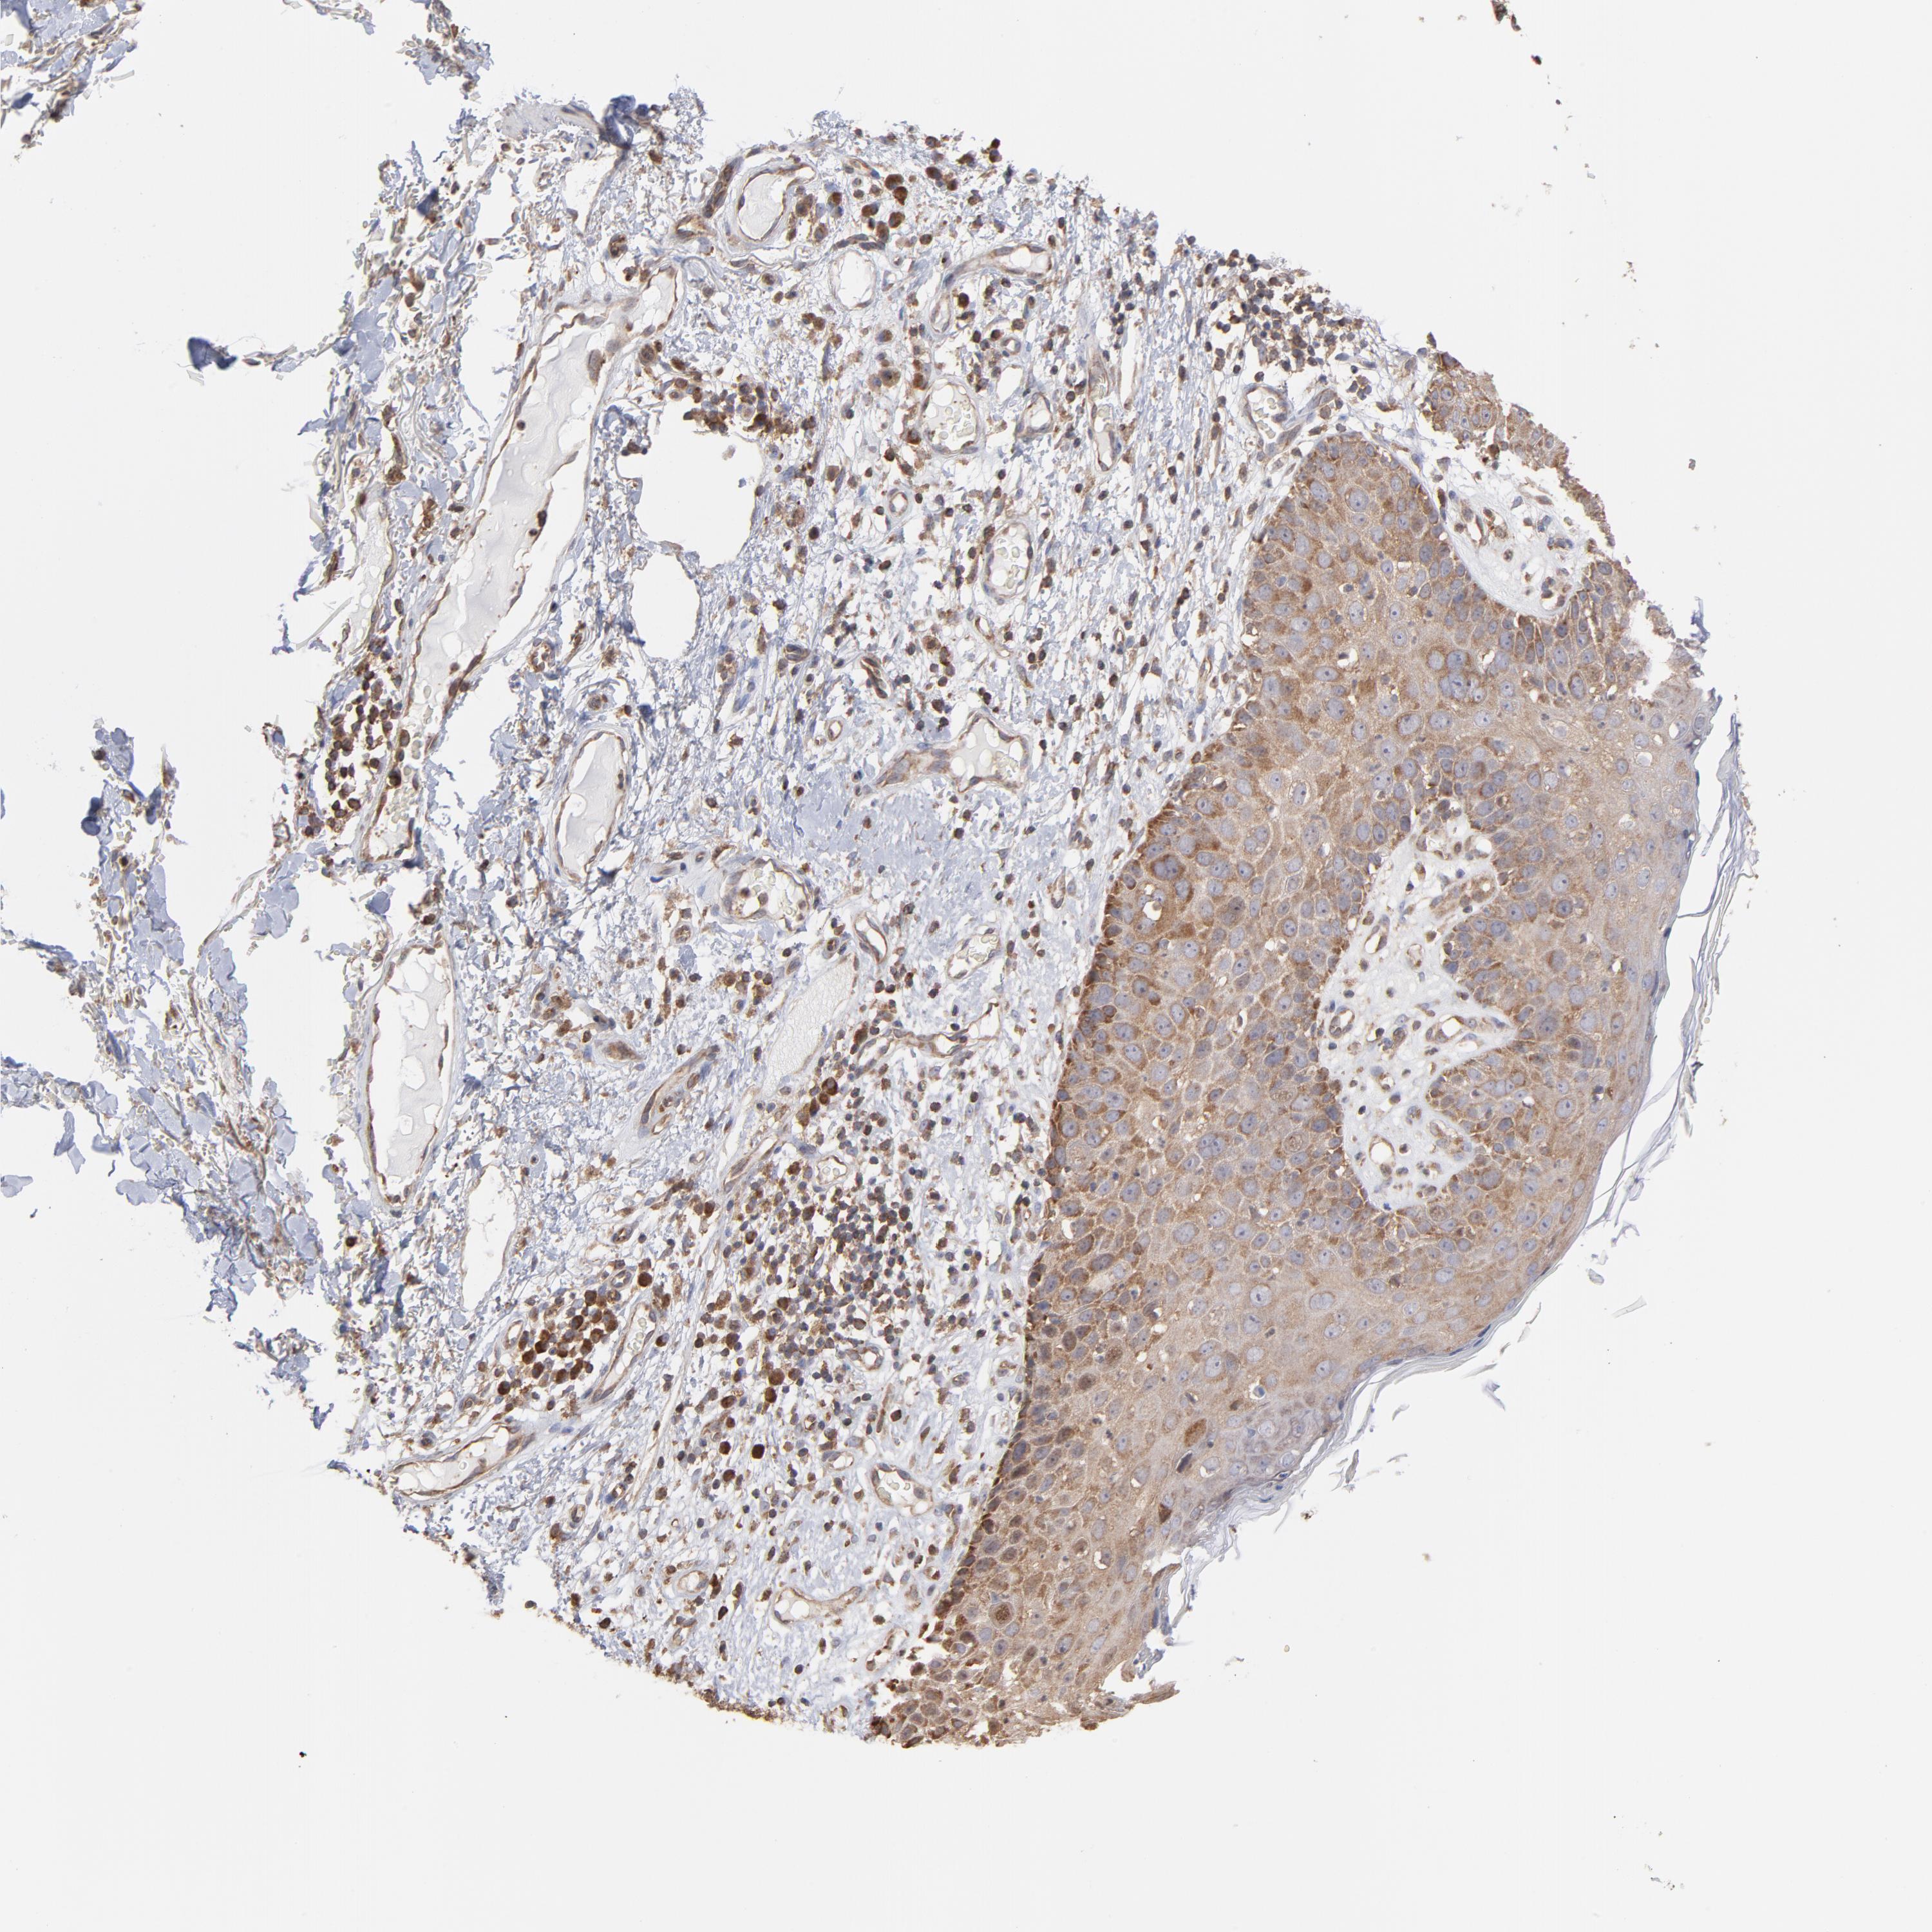

SKIN CANCER - Protein expressioni

A mouse-over function shows sample information and annotation data. Click on an image to view it in a full screen mode. Samples can be filtered based on level of antibody staining by selecting one or several of the following categories: high, medium, low and not detected. The assay and annotation is described here.

Antibody stainingi

Antibody staining in the annotated cell types in the current human tissue is reported as not detected, low, medium, or high, based on conventional immunohistochemistry profiling in selected tissues. This score is based on the combination of the staining intensity and fraction of stained cells.

Each image is clickable and will lead to virtual microscopy that enables deeper exploration of all samples and also displays staining intensity scores, fraction scores and subcellular localization as well as patient and tissue information for each sample.

Antibody CAB009337

Basal cell carcinoma